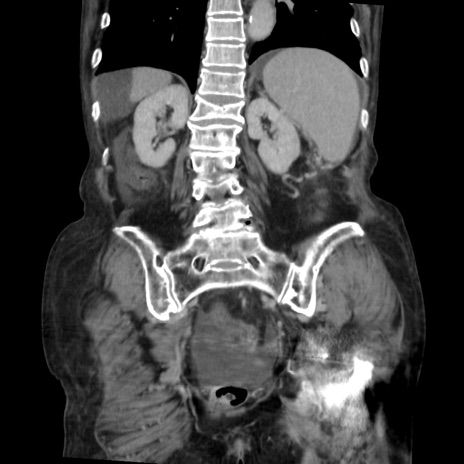

症例31(冠状断像)

【症例】80歳代 女性

【主訴】腹部膨満感

【現病歴】他院にて肝硬変にてフォロー中。1週間前から便秘、腹部膨満感、臍部腫瘤あり受診となる。

【既往歴】肝硬変

【身体所見】腹部膨隆あり、皮膚変化なし、疼痛なし。

【データ】WBC 4600、CRP 0.25